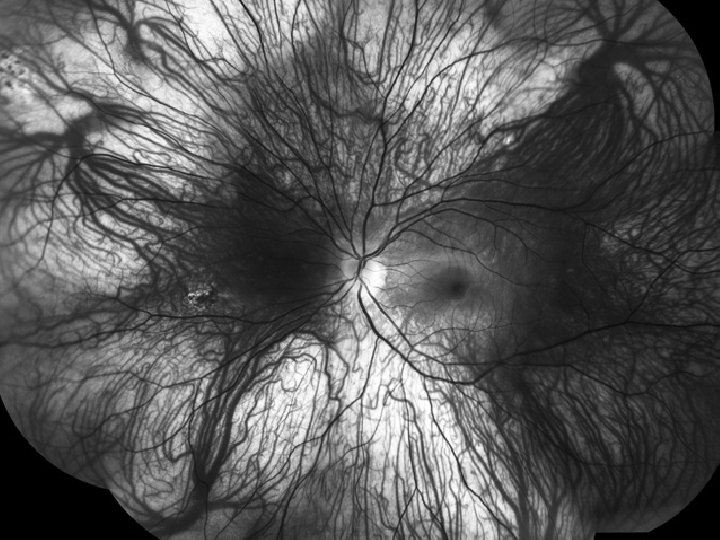

Normal Retina with normal choroidal markings visible through the translucent retina.

Example of both retinal vessels and choroidal vessels (choroidal markings) easily visible (A red-free photograph, that makes blood appear “black” is a patient with an extremely thin retina) (also great example of vortex veins!)